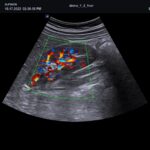

| Softwares Disponibles: | Shear Wave Elastography (SWE), Volume SRI, X+ pSWE (Point Shear Wave Elastography, X+ Assistant, X + Auto IVC, AutoEF, CEUS, X+Compare, Brilliant Flow, TIC Analysis, |

| Transductores: | Lineal 3~19MHz (256 cristales), Lineal 10~25MHz, Convexo 1~7MHz, Endocavitario 2~11MHz, Convexo Volumétrico 1~8MHz, Endocavitario Volumétrico 3~10MHz, Phased Array (alta resolución), TEE |